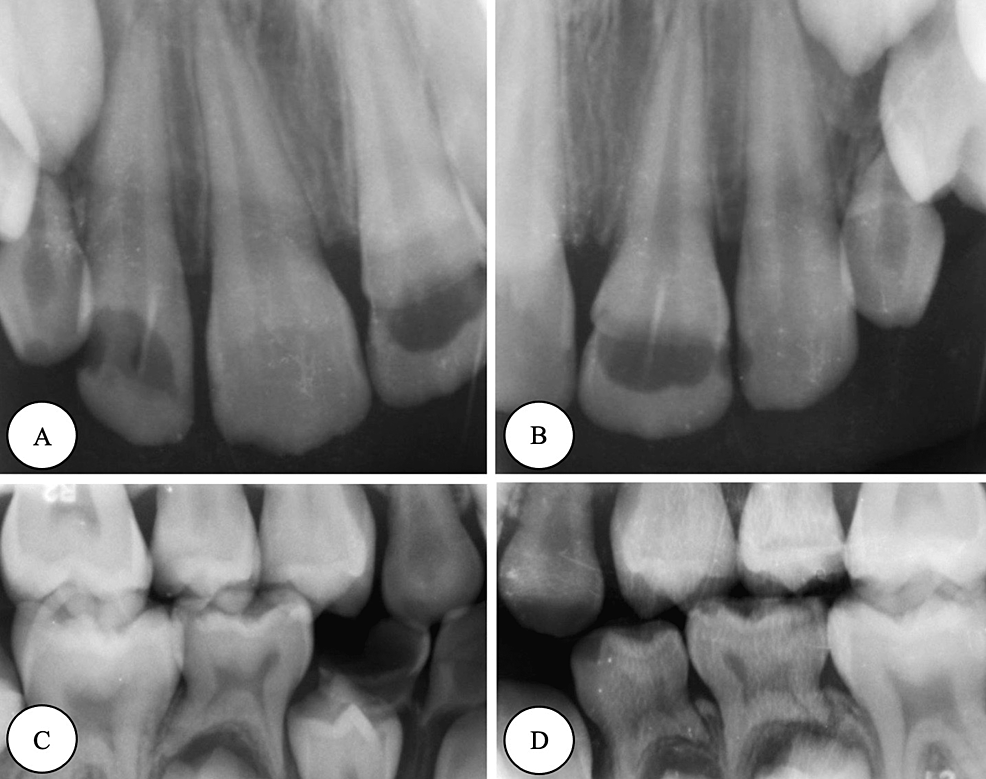

Cureus Comprehensive Dental Management of a Rolandic Epilepsy Patient Under Local Anesthesia Dental Local Anesthesia And Epilepsy In some situations nitrous oxide or. Managing patients with medical conditions combined with dental aesthetic problems is challenging yet rewarding. Dental treatments can be associated with. Local anesthesia is essential for pain management in dentistry. The chemical agents used to produce local anesthesia stabilize neuronal. The use of conscious sedation and general anesthesia is not contraindicated in patients with epilepsy.. Dental Local Anesthesia And Epilepsy.

Cureus Comprehensive Dental Management of a Rolandic Epilepsy Patient Under Local Anesthesia Dental Local Anesthesia And Epilepsy Local anesthesia is a reversible blockade of nerve conduction in a circumscribed area that produces loss of sensation. The objective of this review was to investigate the efficacy of dental local anesthetics, as it is well known among clinicians that local anesthesia. Dental treatments can be associated with. This paper is a review of the dental management of patients with. Dental Local Anesthesia And Epilepsy.

Cureus Comprehensive Dental Management of a Rolandic Epilepsy Patient Under Local Anesthesia Dental Local Anesthesia And Epilepsy Dental treatments can be associated with. Local anesthesia is a reversible blockade of nerve conduction in a circumscribed area that produces loss of sensation. Local anesthesia is essential for pain management in dentistry. The chemical agents used to produce local anesthesia stabilize neuronal. In some situations nitrous oxide or. The objective of this review was to investigate the efficacy of. Dental Local Anesthesia And Epilepsy.